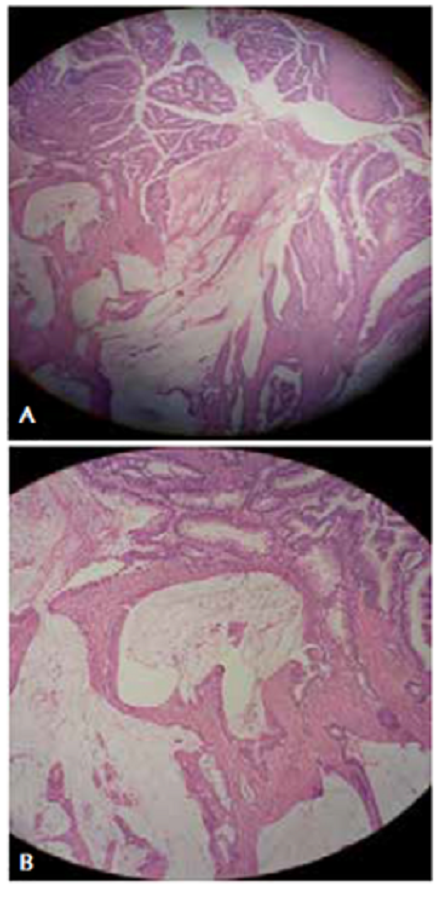

En la laparotomía exploratoria se encontró una intususcepción del colon derecho, que atravesaba el colon transverso y alcanzaba parte del colon descendente (figura 2). Tras la reducción manual, se palpó una masa bien delimitada, de 5 cm de diámetro, en el colon transverso. Se practicaron una hemicolectomía derecha con principios oncológicos y una anastomosis ileocólica. El periodo posoperatorio transcurrió sin complicaciones y el paciente fue dado de alta a los cinco días de la intervención. El examen histopatológico del colon resecado reveló una masa de 2 x 5 cm correspondiente a un adenocarcinoma mucinoso (figura 3).

Por persistencia del dolor abdominal, se decidió practicar una laparotomía exploratoria, en la que se encontró una intususcepción ileocólica (figura 5). Tras la reducción manual, se visualizó una masa de 6 cm de diámetro, aproximadamente, en la válvula ileocecal. Se optó por una hemicolectomía oncológica derecha y anastomosis ileocólica. El periodo posoperatorio transcurrió sin complicaciones y el paciente fue dado de alta a los siete días de la intervención. El examen histopatológico de la pieza quirúrgica reveló una masa de 4 x 6 cm correspondiente a un tumor del estroma gastrointestinal (GIST) (figura 6).